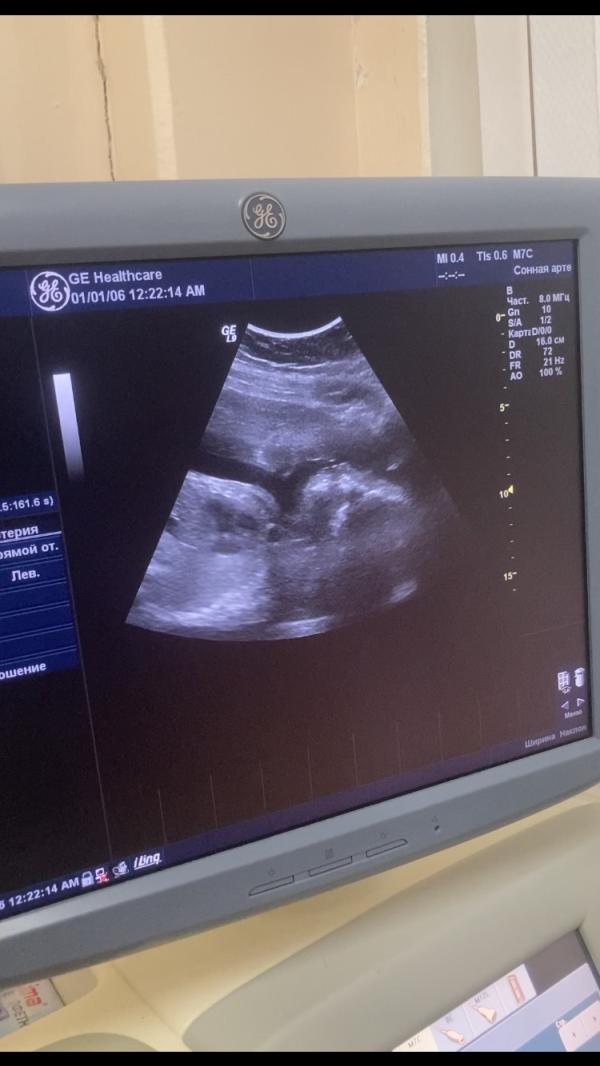

27 недель: как справиться с болью в лобке при беременности?

Нам 27 неделек😍